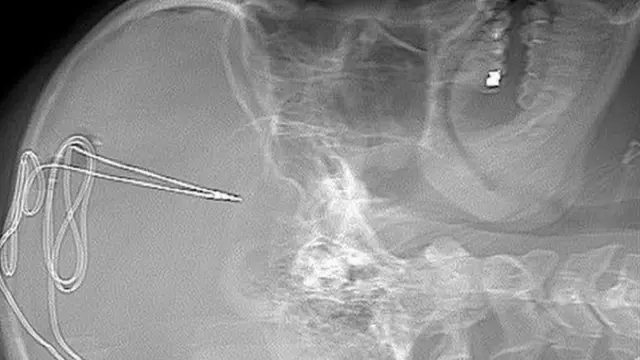

ويبدأ الإعداد لهذه الجراحة بسلسلة من فحوصات مسح الدماغ، بعدها يبدأ الجراحون في ثقب الجمجمة لإدخال أنبوب كهربائي متناهي الصغر لا يتجاوز حجمه ملليمتر في منطقة محددة من المخ وتساعد المريض على التحكم في الدوافع مثل الإدمان والتحكم في الذات.

كما تُزرع بطارية تحت عظام الترقوة ثم يخضع نشاط المخ للمراقبة عن بعد على يد فريق من الأطباء البشريين، والنفسيين، وخبراء الإدمان لتحديد إذا ما كانت الرغبة في تناول المخدر تتراجع أم لا.